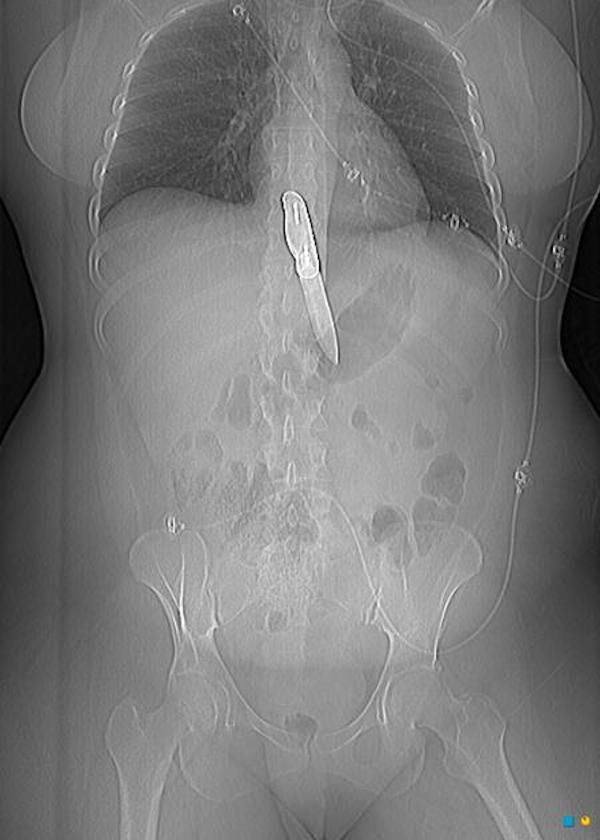

13 / 15Ołówek

Przykra sprawa.